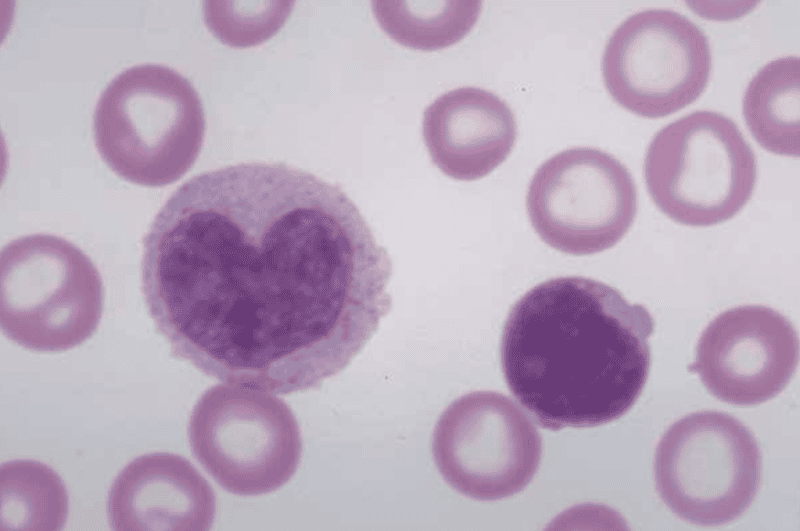

Monocyte

[Function of a] Monocyte

Develop into macrophages in tissues and phagocytize pathogens or debris

[Definition of] Leukocytosis

Increase in the number of white blood cells in blood, especially during infection

[Definition of] Leucopenia

Reduction in the number of white blood cells in blood, typical of various diseases

[Definition of] Leukemia

Uncontrolled growth of immature, abnormal (non-functional) leukocytes

Order of Leukocytes from most numerous to least numerous

Neutrophil --> Lymphocyte --> Monocyte --> Eosinophil --> Basophil

(Never Let Monkeys Eat Bananas)